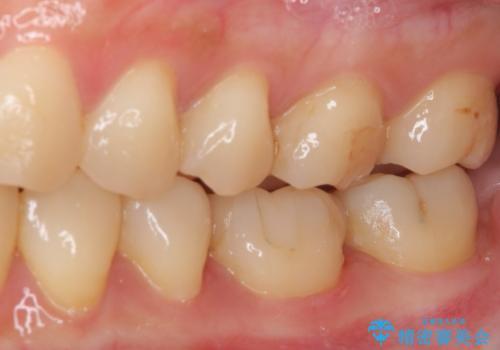

- 下の奥歯(右下7・左下7)にあって目立ってしまう銀歯を白くしたいとのことで来院された患者様です。

セラミックインレーにて修復治療を行うこととしました。

セラミックインレーを装着したことで、とても自然な仕上がりとなりました。

患者様も大きく口を開けても気にならなくなった、大変喜んでくださいました。